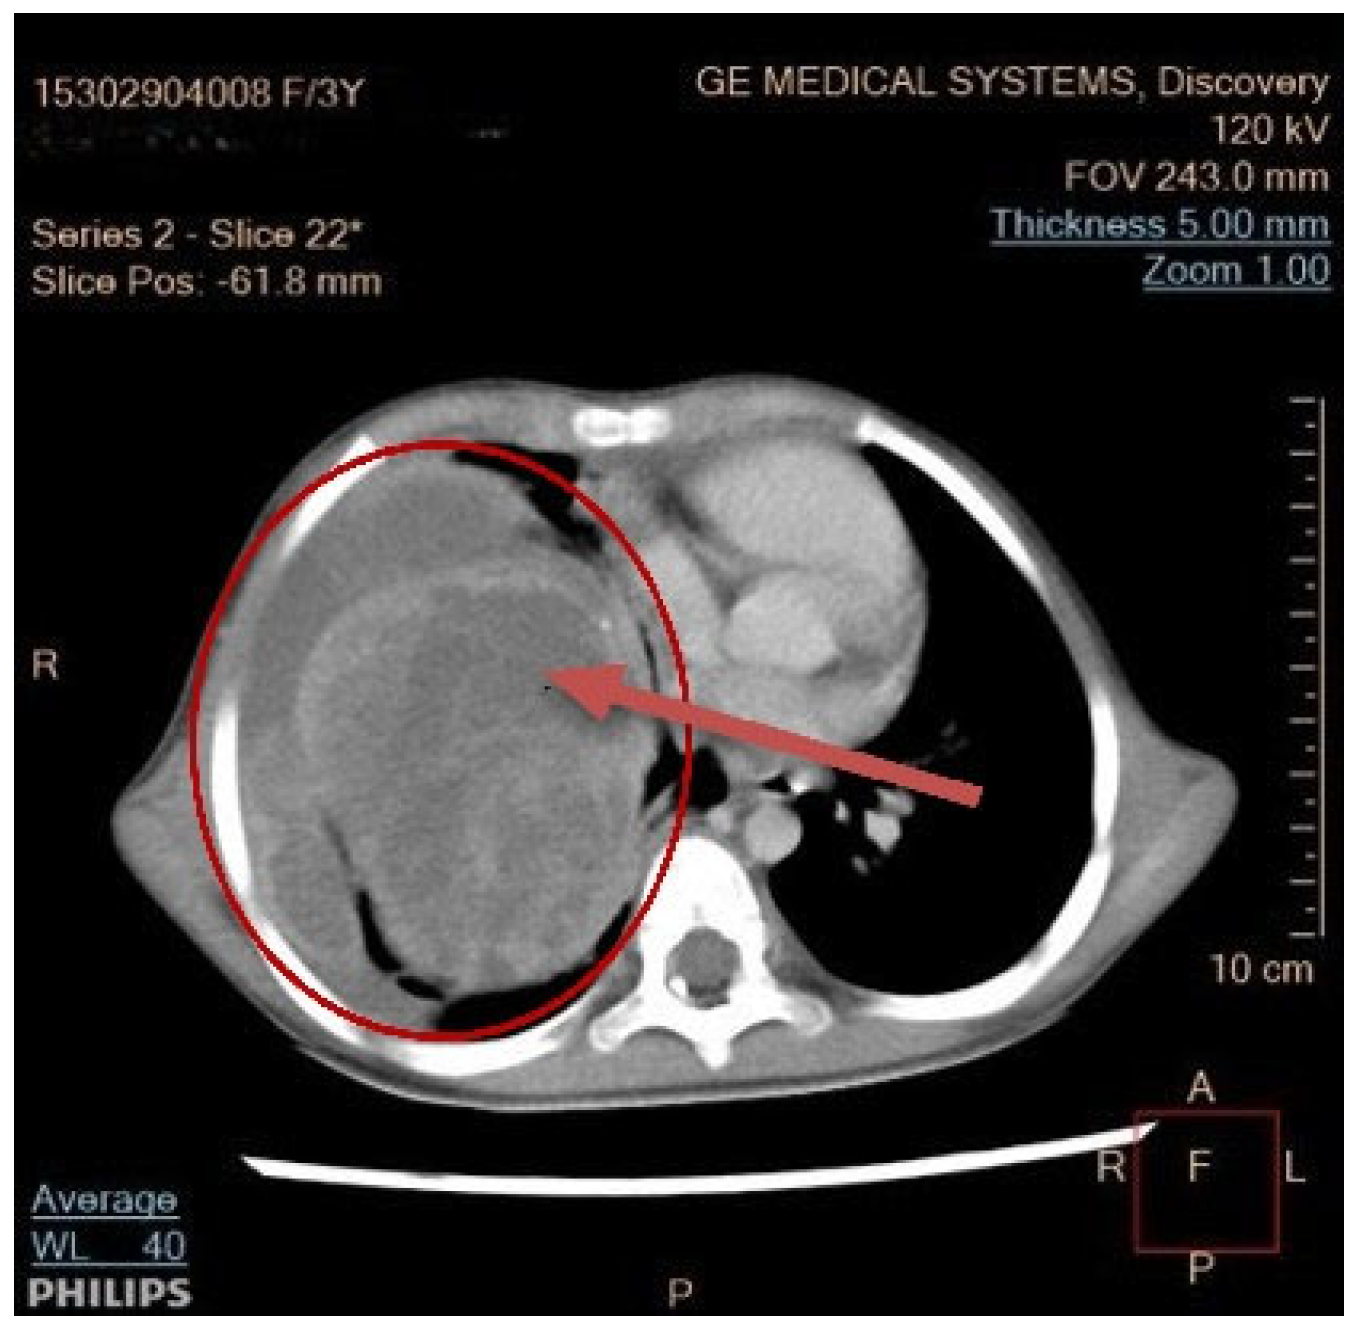

Seven children had a tumor located on the left side of the chest, and eight children on the right side. In seven children, the dimensions of the tumor were >10 cm; in five, they measured 5–10 cm; and in two patients, they were below 5 cm. In one patient, the dimensions were difficult to assess due to the occurrence of a massive pneumothorax. No bilateral lesions were found. Typical radiological findings are shown on Figure 2, Figure 3 and Figure 4.

Figure 3. Enhanced contrast of CT scan. The arrow indicates a large 8 × 9 × 16 cm heterogeneously enhancing solid mass in the right hemithorax with pleural effusion.